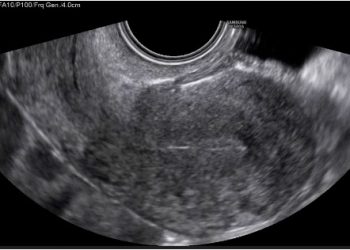

Per il mese di Gennaio SIEOG Giovani e il Comitato di Studio in Ecografia Ginecologica presentano il Webinar sulla Patologia...